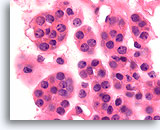

Afbeelding 18

Folliculair neoplasma, schildklier FNA, celblok.

De uniformiteit van het cytoplasma, de robuuste cilindrische epitheelcellen, de microfolliculaire ordening, de afwezigheid van hemosiderine en de eenvormigheid van het colloïde pleiten in dit ene veld voor een folliculair neoplasma.

40X

Afbeelding 18

Folliculair neoplasma, schildklier FNA, celblok.

De uniformiteit van het cytoplasma, de robuuste cilindrische epitheelcellen, de microfolliculaire ordening, de afwezigheid van hemosiderine en de eenvormigheid van het colloïde pleiten in dit ene veld voor een folliculair neoplasma.

40X